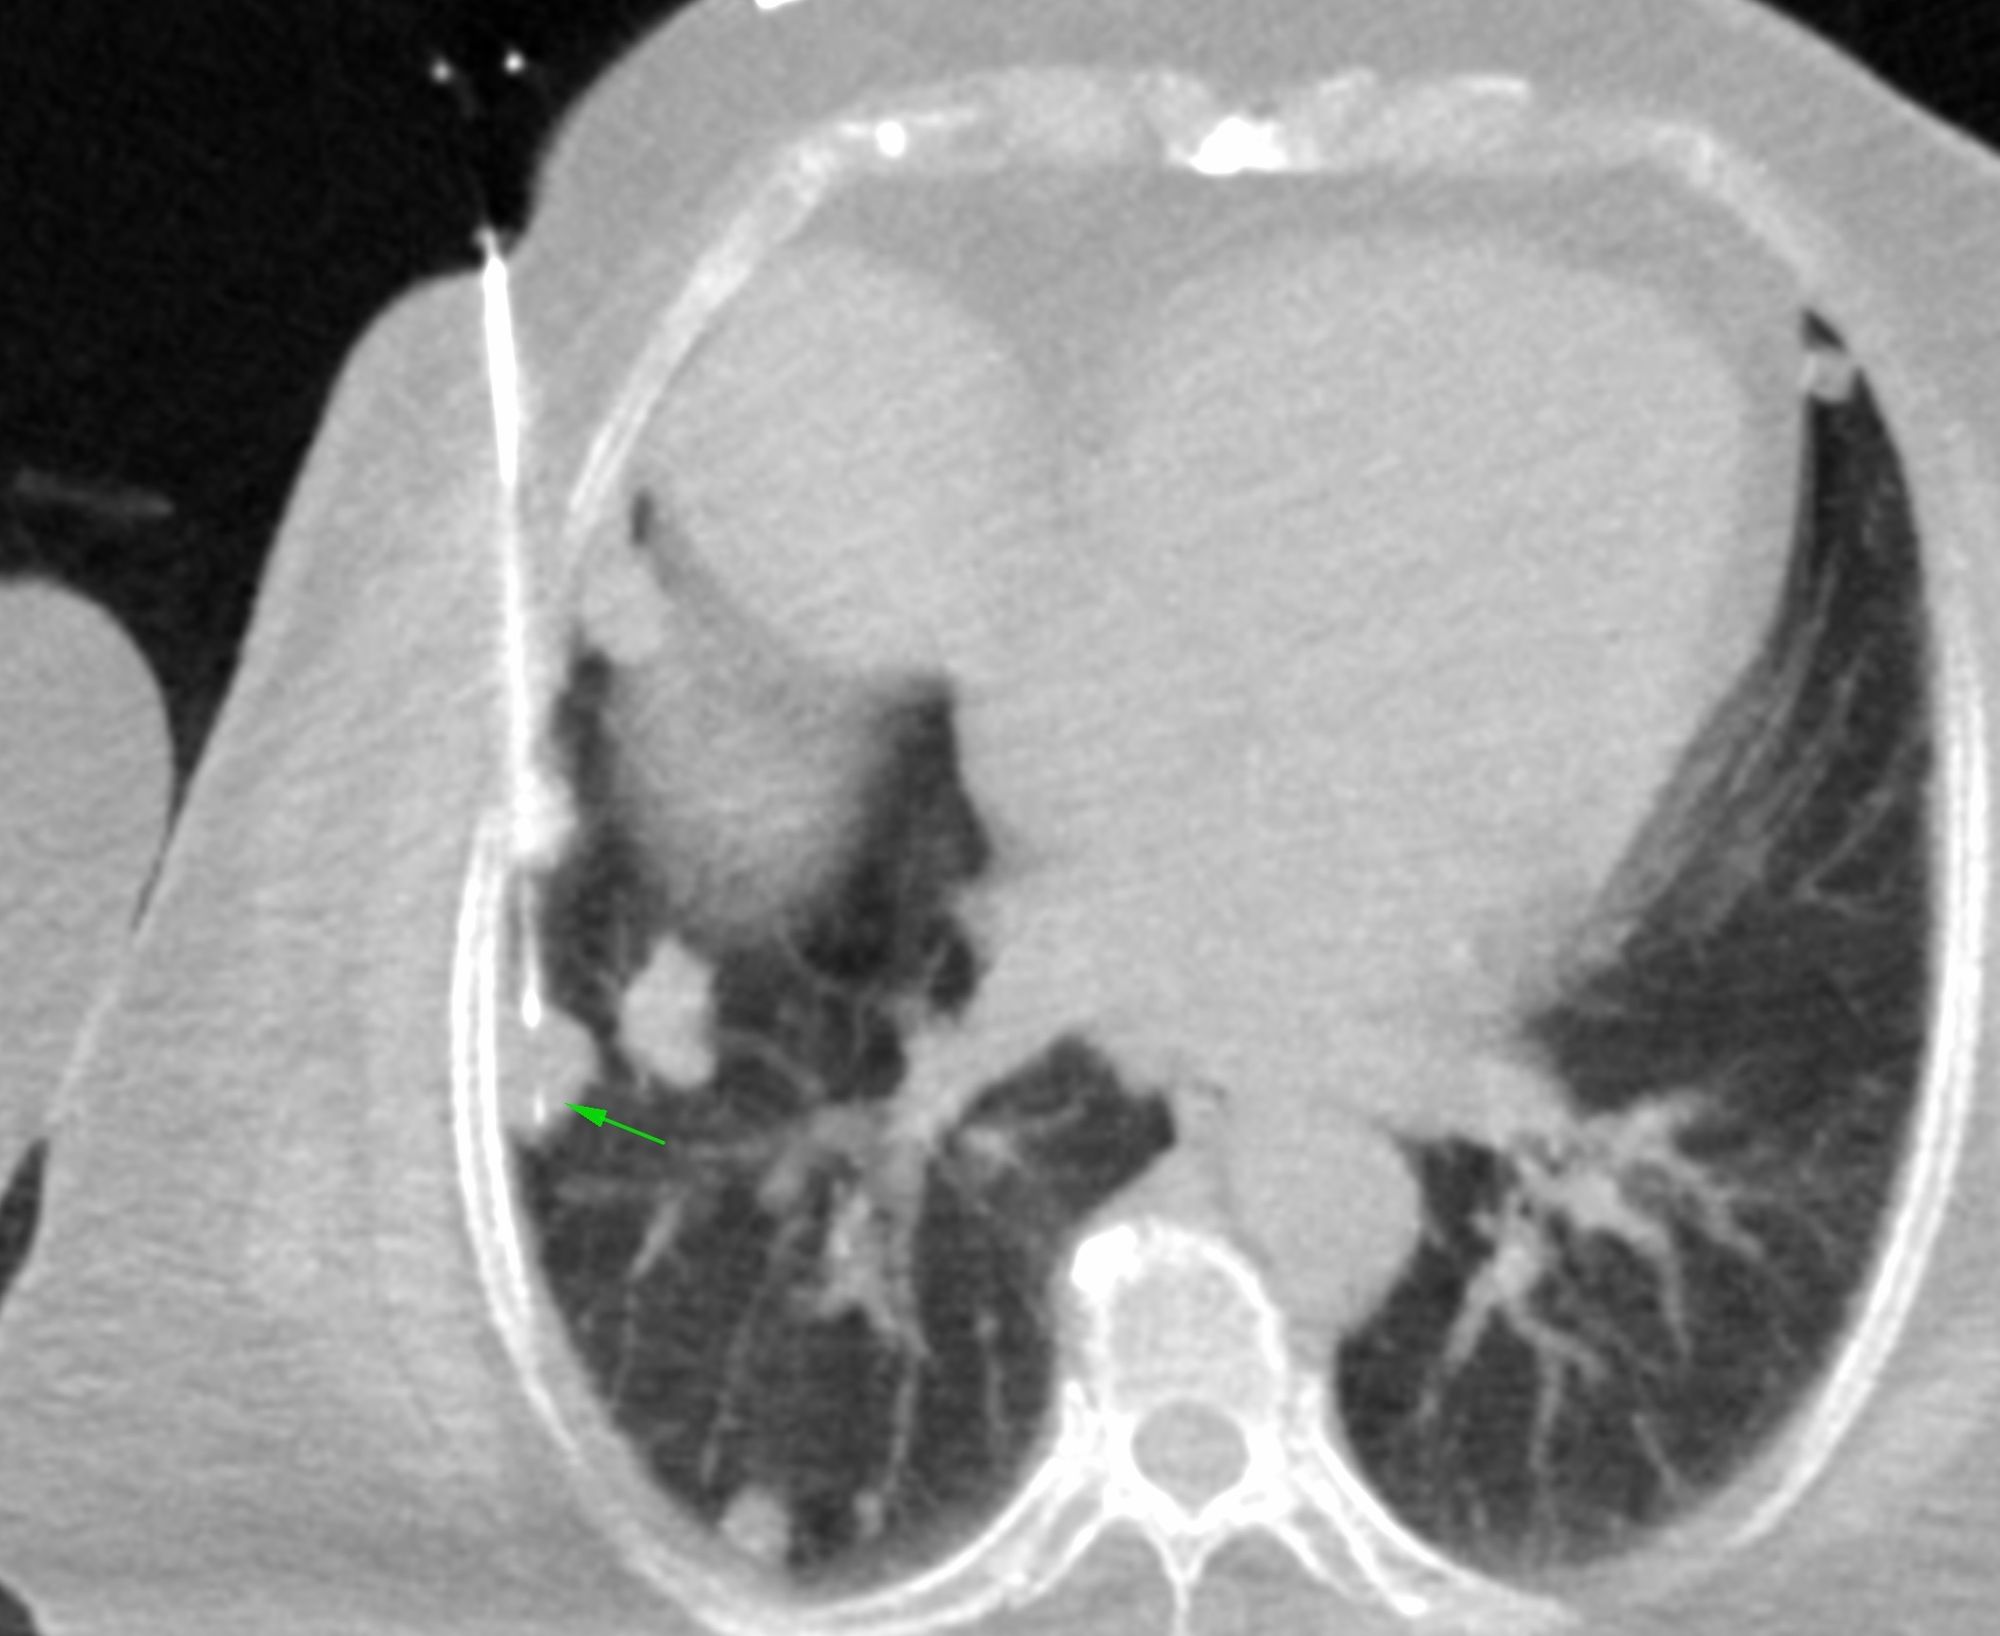

Case 76: When the Biopsy Needle is "Breathed Out" Of the Lesion

Bhavin Jankharia - 21 January 2022